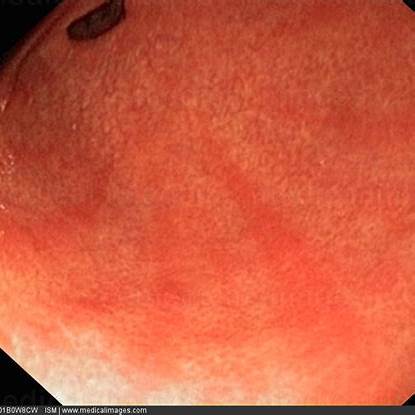

장상피화생은 내시경 검사와 조직검사를 통해 확진됩니다.

특히 조직검사를 통해 세포 변화를 직접 확인할 수 있어요.

저는 내시경 결과에서 위 점막 색이 변화된 부위를 조직검사로 확인했고, 헬리코박터균 검사도 함께 진행했습니다.